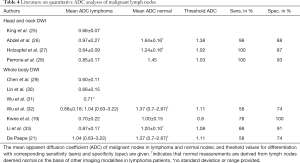

Literature review

The ADC values and respective threshold values for differentiation derived from single-slice ROI measurements on small field of view head and neck MRI and other WB-DWI studies are presented in Table 4.

Our study applies an algorithm to identify and segment diseased nodal regions across the body, which allows the gADC of all lymphomatous nodes to be characterised compared with a large population of benign lymph nodes in normal volunteers. We found that gADC histogram parameters were able to distinguish between diseased lymphomatous nodes and those of healthy volunteers. The former showed significantly lower gADC values. The gADC 10th centile performed best for discriminating between lymphoma patients and healthy volunteers. For discriminating individual nodal volumes as diseased or healthy, we found the 10th centile value to be of good discriminatory value. Although, diagnostic performance was not significantly superior to mean ADC, this could have diagnostic implications. Previous works on different entities have described the merits of the 10th centile ADC as an oncologic imaging biomarker, which warrants prospective performance comparison of 10th centile, mean and median ADC (38).

In contrast to the reviewed small field of view and WB-DWI literature on quantitative DWI for lymph node characterisation, we evaluated ADC measurements derived from a semi-automatic segmentation of lymph node volumes. In metastatic bone disease this approach was shown to offer good reproducibility (39). The calculated gADC and ADC values of normal and diseased nodes are comparable with ADC measurements recorded in previous studies.

Kwee et al. published the only prior study comparing malignant nodes with normal nodes of healthy patients employing WB-DWI in lymphoma patients and extended field of view DWI in healthy individuals. ADC measurements were derived from manually placed single slice ROIs. ROIs were placed in FDG-PET/CT positive lymph nodes in lymphoma patients and in the largest lymph node of healthy patients (19). DWI of the thorax and abdomen were not included in healthy patients compared to a true WB-DWI protocol employed in our volunteers. This may have contributed to a higher mean nodal gADC in our healthy volunteers, as well as a higher gADC threshold in our study compared with those reported by Kwee et al. Lymph nodes of the thorax and abdomen are prone to be affected by bulk motion, which can increase ADC values due to partial volume effects.It needs to be noted that our measured gADC values were within the standard deviation of the ADC measurements reported by Kwee et al. Moreover, ADC values are known to have a variability of 5–12%, increasing with smaller volume measurements (40,41). The general agreement of gADC measurements of lymph nodes with previous literature using regional ADC measurements shows that a volume based approach is feasible and reliable while allowing to include a larger disease volume. In a future prospective scenario, the software could allow for whole-body lymph node region delineation and automated identification of suspicious nodal regions according to their ADC histogram characteristics and verify the derived ADC cut-off values of this study.